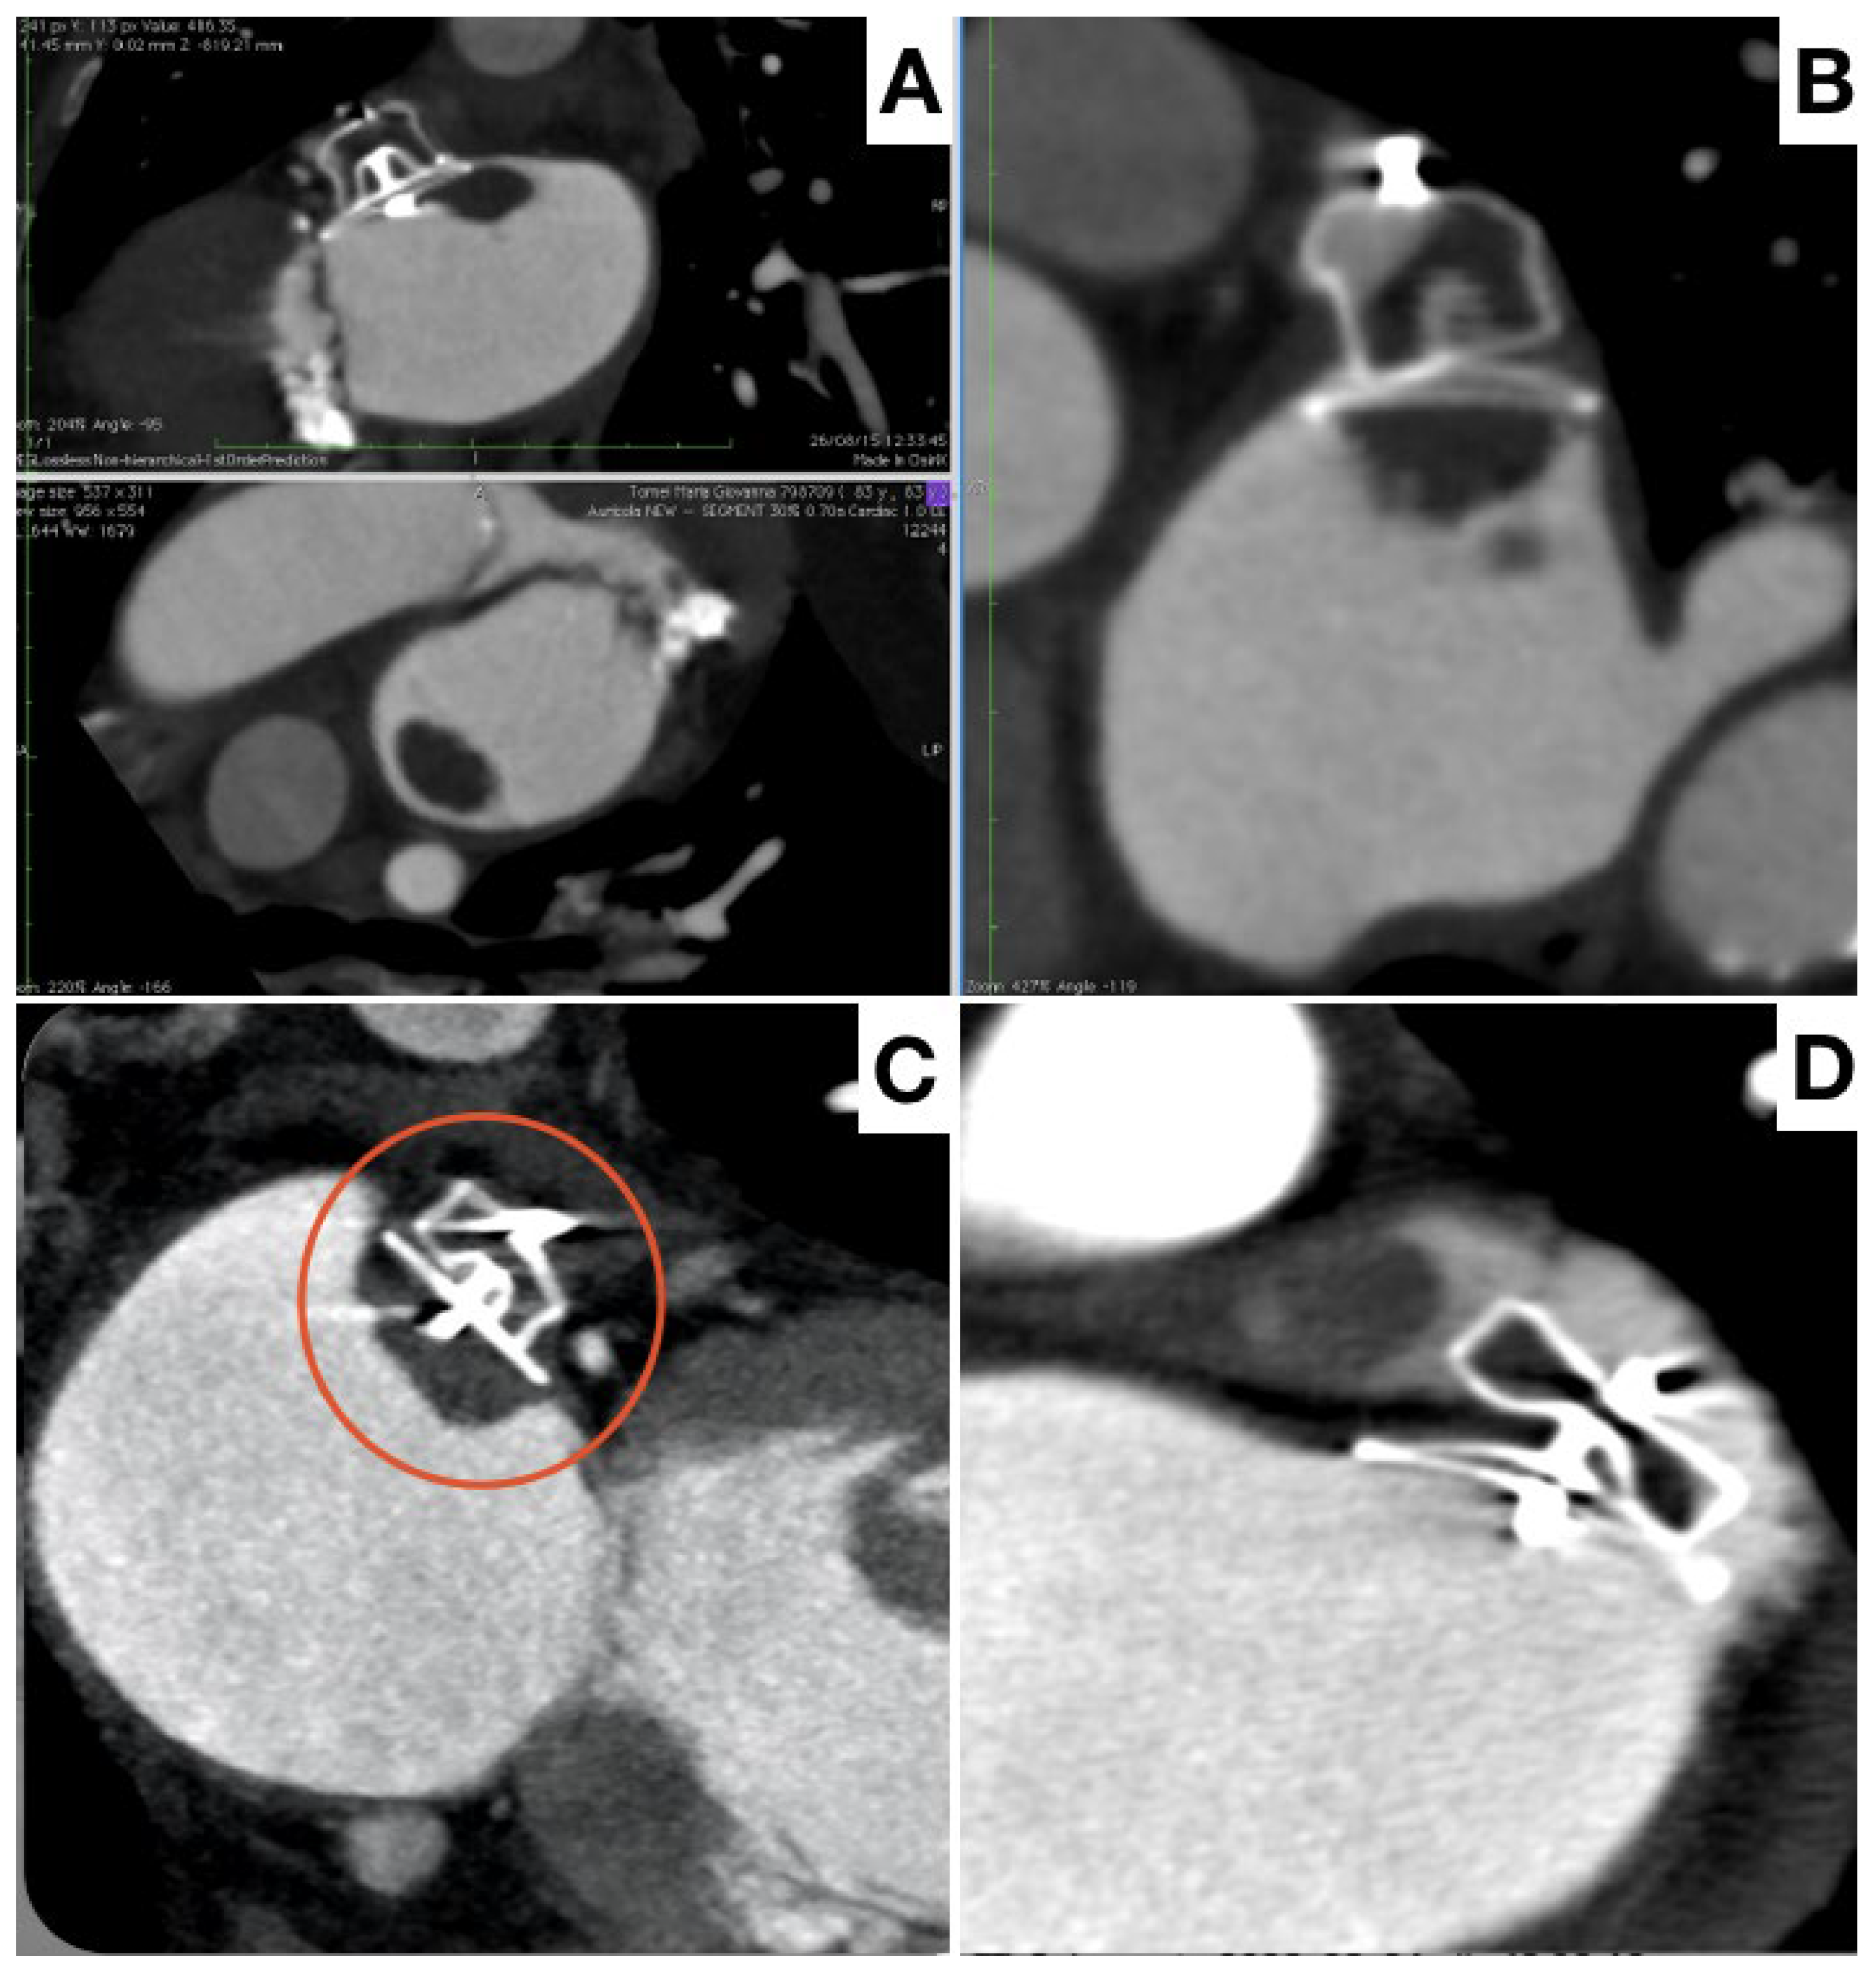

- Korsholm, K.; Jensen, J.M.; Nørgaard, B.L.; Nielsen-Kudsk, J.E. Detection of Device-Related Thrombosis Following Left Atrial Appendage Occlusion: A Comparison Between Cardiac Computed Tomography and Transesophageal Echocardiography. Circ. Cardiovasc. Interv. 2019, 12, e008112. [Google Scholar] [CrossRef] [PubMed]

- Clemente, A.; Avogliero, F.; Berti, S.; Paradossi, U.; Jamagidze, G.; Rezzaghi, M.; Della Latta, D.; Chiappino, D. Multimodality imaging in preoperative assessment of left atrial appendage transcatheter occlusion with the Amplatzer Cardiac Plug. Eur. Heart J. Cardiovasc. Imaging 2015, 16, 1276–1287. [Google Scholar] [CrossRef]

- Korsholm, K.; Jensen, J.M.; Nørgaard, B.L.; Samaras, A.; Saw, J.; Berti, S.; Tzikas, A.; Nielsen-Kudsk, J.E. Peridevice Leak Following Amplatzer Left Atrial Appendage Occlusion: Cardiac Computed Tomography Classification and Clinical Outcomes. JACC Cardiovasc. Interv. 2021, 14, 83–93. [Google Scholar] [CrossRef]